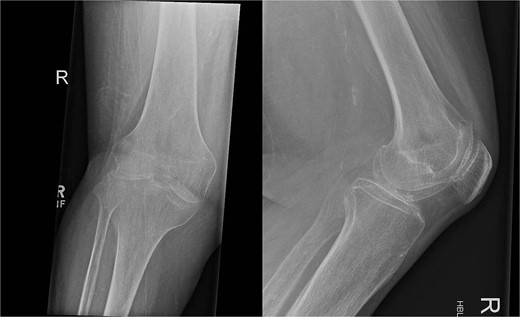

Over the following month, the skin above the fractured patella became necrotic, resulting in an open discharging wound. It was now clear that infection was the issue. With Orthoplastics involvement, she underwent multiple tissue samplings, patellectomy, removal of implants, and insertion of an antibiotic impregnated cement spacer (Fig. 3). Over the ensuing days the infection was uncontrollable despite further debridement and appropriate multi-drug antibiotic therapy. Following a multi-disciplinary team decision, a staged Above Knee Amputation (AKA) was performed (Fig. 3) with negative pressure dressings applied in the interim. Patient was discharged 4 weeks later on achieving closure of the stump. Mobility at discharge was limited to hoist transfers. Unfortunately, the patient passed away 8 weeks later.

On the left X-ray of the knee after removal of prosthesis and insertion of antibiotic-impregnated cement spacer and on the right X-ray of the stump following amputation.